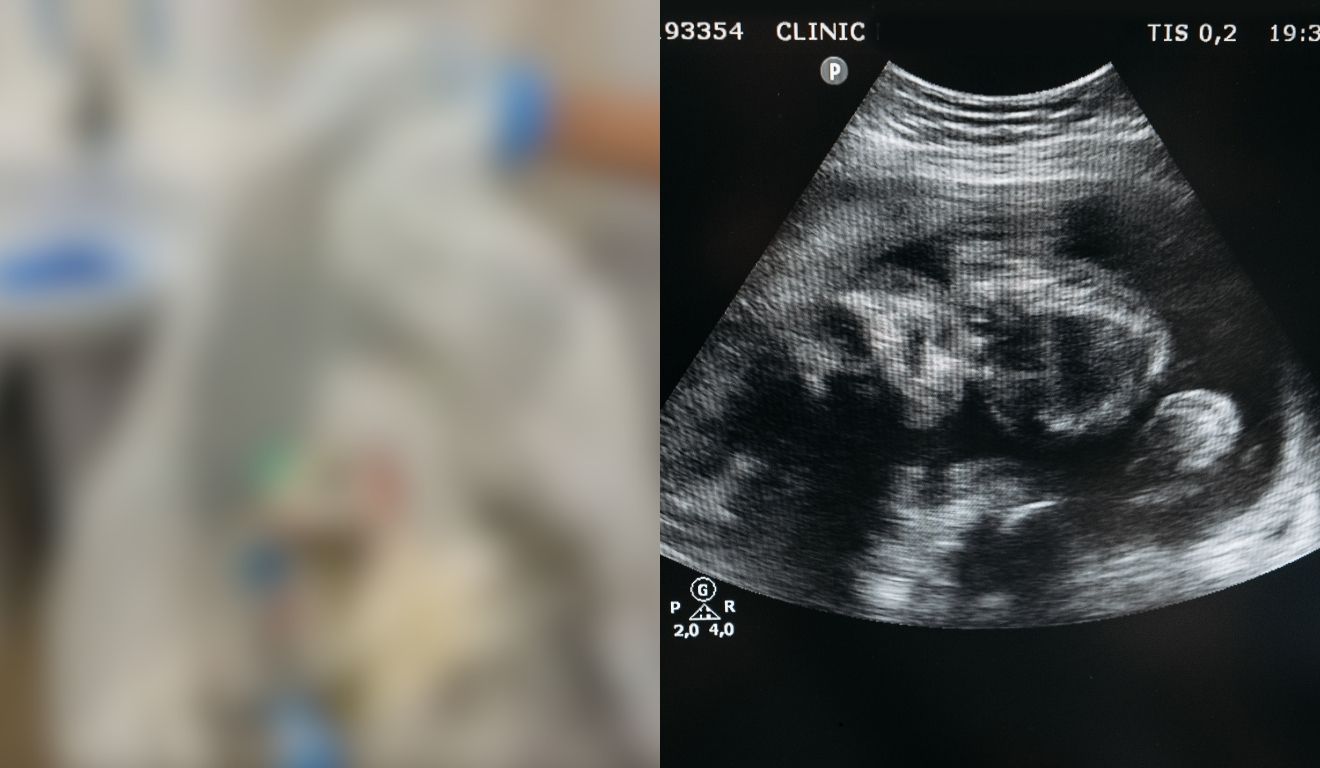

Um casal foi preso e uma jovem de 20 anos morreu após uma tentativa de aborto clandestino em um motel. O caso aconteceu na cidade de Ceres (GO), na última sexta-feira (1°).

De acordo com a Polícia Civil de Goiás (PCGO), o homem que foi preso, que é cirurgião-dentista, seria pai do bebê. Ele e a namorada, uma técnica em enfermagem, teriam ido com a jovem até o motel para realizar o procedimento.

Em depoimento, os investigados afirmaram que sabiam dos riscos que a grávida passaria ao realizar o abordo clandestino no motel e que tinham ciência de que o procedimento era ilegal. Além disso, a técnica de enfermagem relatou que aplicou o medicamento abortivo na vítima.

Conforme o relato, o casal teria tentado realizar manobras de socorro quando a gestante começou a passar mal. Ela foi levada à Unidade de Pronto Atendimento (UPA) da região com sinais de parada neurológica.